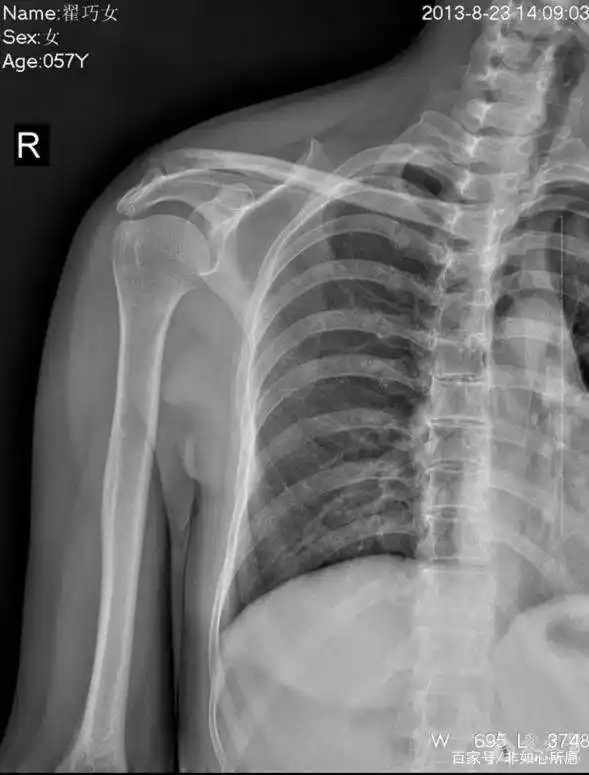

一张肩关节的片子,帮我看看